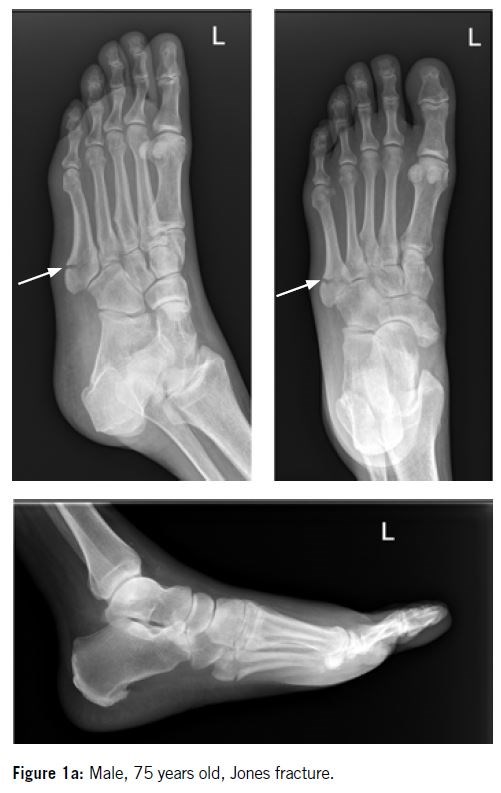

Several classification systems are used to describe proximal fractures of the fifth metatarsal. Sir Robert Jones first described the “Jones fracture” in a small case series of four patients, including himself, as a fracture at the metadiaphyseal junction.

The Lawrence and Botte classification system (Figure 3) is commonly used and holds prognostic value based on fracture zone distributions. The proximal fifth metatarsal is divided into three zones:

Zone II / metaphyseal - diaphyseal junction   (Figure 5)